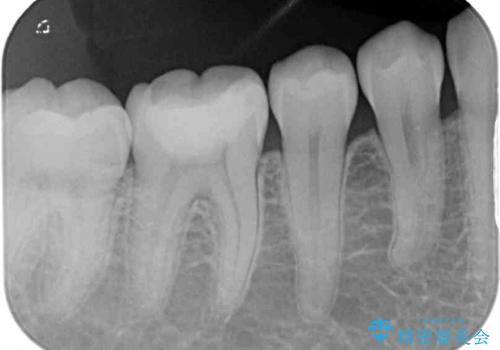

むし歯治療した歯にセラミックを入れたい セラミックインレー修復

- 他院にてむし歯の治療をし、当院にてセラミックを入れたいとのことで来院された患者様です。

むし歯がないか確認し、セラミックインレーにて修復することとしました。